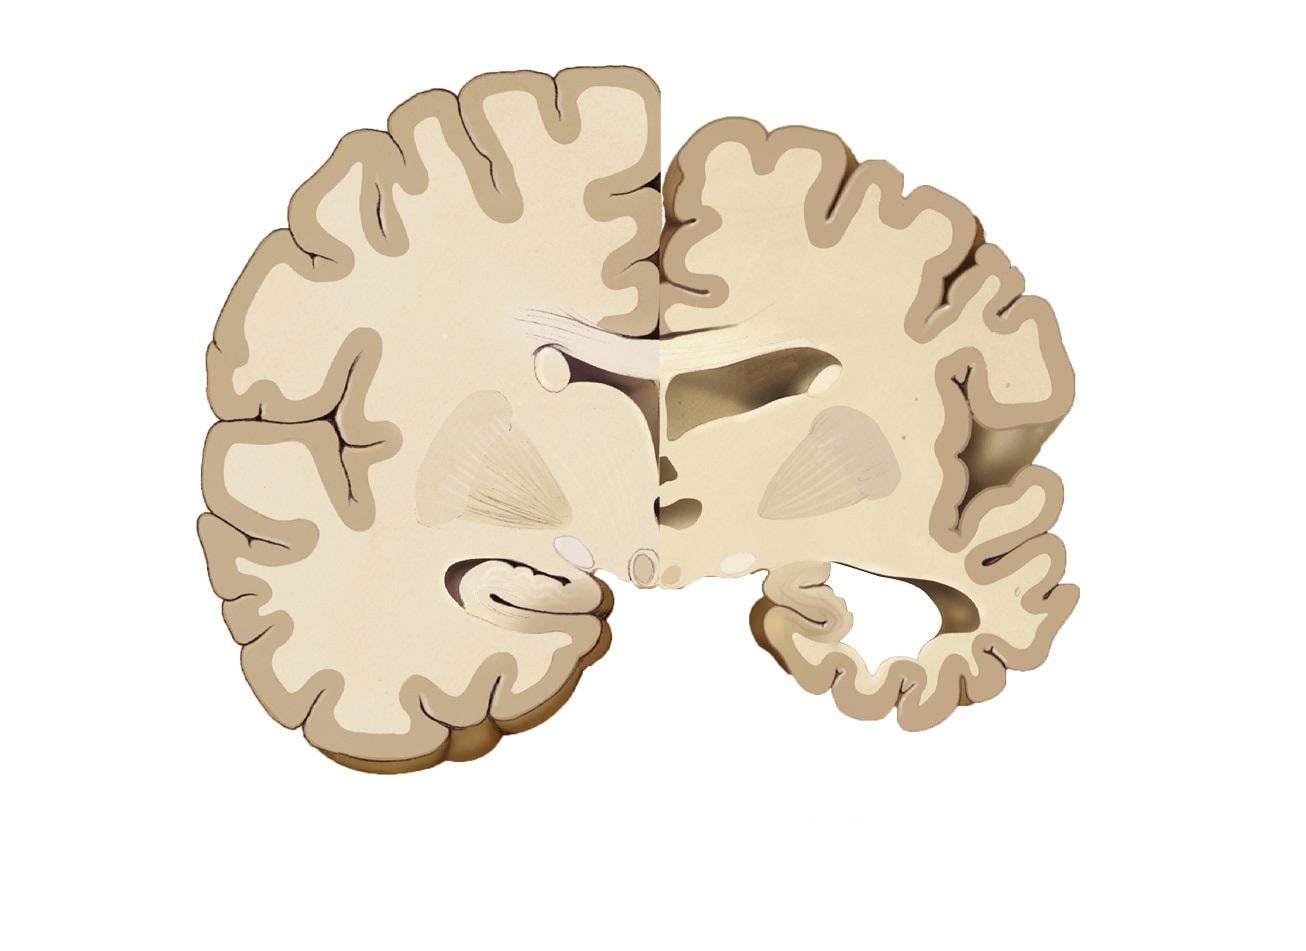

該項由退伍軍人醫學組織及史丹福大學進行的研究,共分析68名年齡介乎28至70歲的酗酒患者,結果發現與沒有酗酒精的人相比,患有酗酒問題的人,整個大腦的皮質體積都較小。同時,飲酒愈多皮質體積的減幅亦愈顯著。

患有酗酒問題的人,整個大腦的皮質體積都較小,或增腦退化風險。